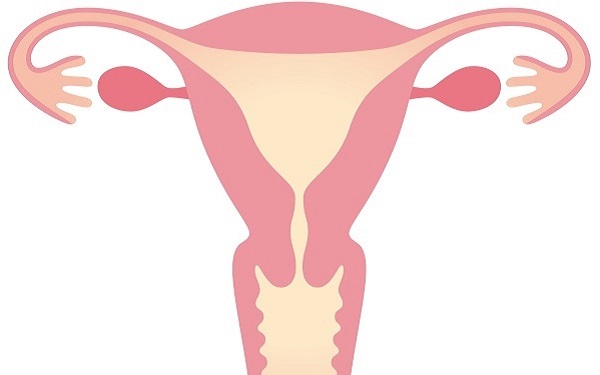

妊娠するには、排卵と月経のサイクルが必要です。それらを促すさまざまなホルモンは、脳や卵巣から分泌され、血液の流れによって体全体に運ばれます。

また東洋医学では、子宮や卵巣に栄養分やホルモンが行き渡らなくなると、月経不順や子宮筋腫、子宮内膜症などの症状を引き起こすと考えられています。

他にも子宮内膜が厚くなりにくく、着床の妨げになるともいわれています。冷え性が妊娠しにくい体の特徴といわれるのは、こういった理由からです。